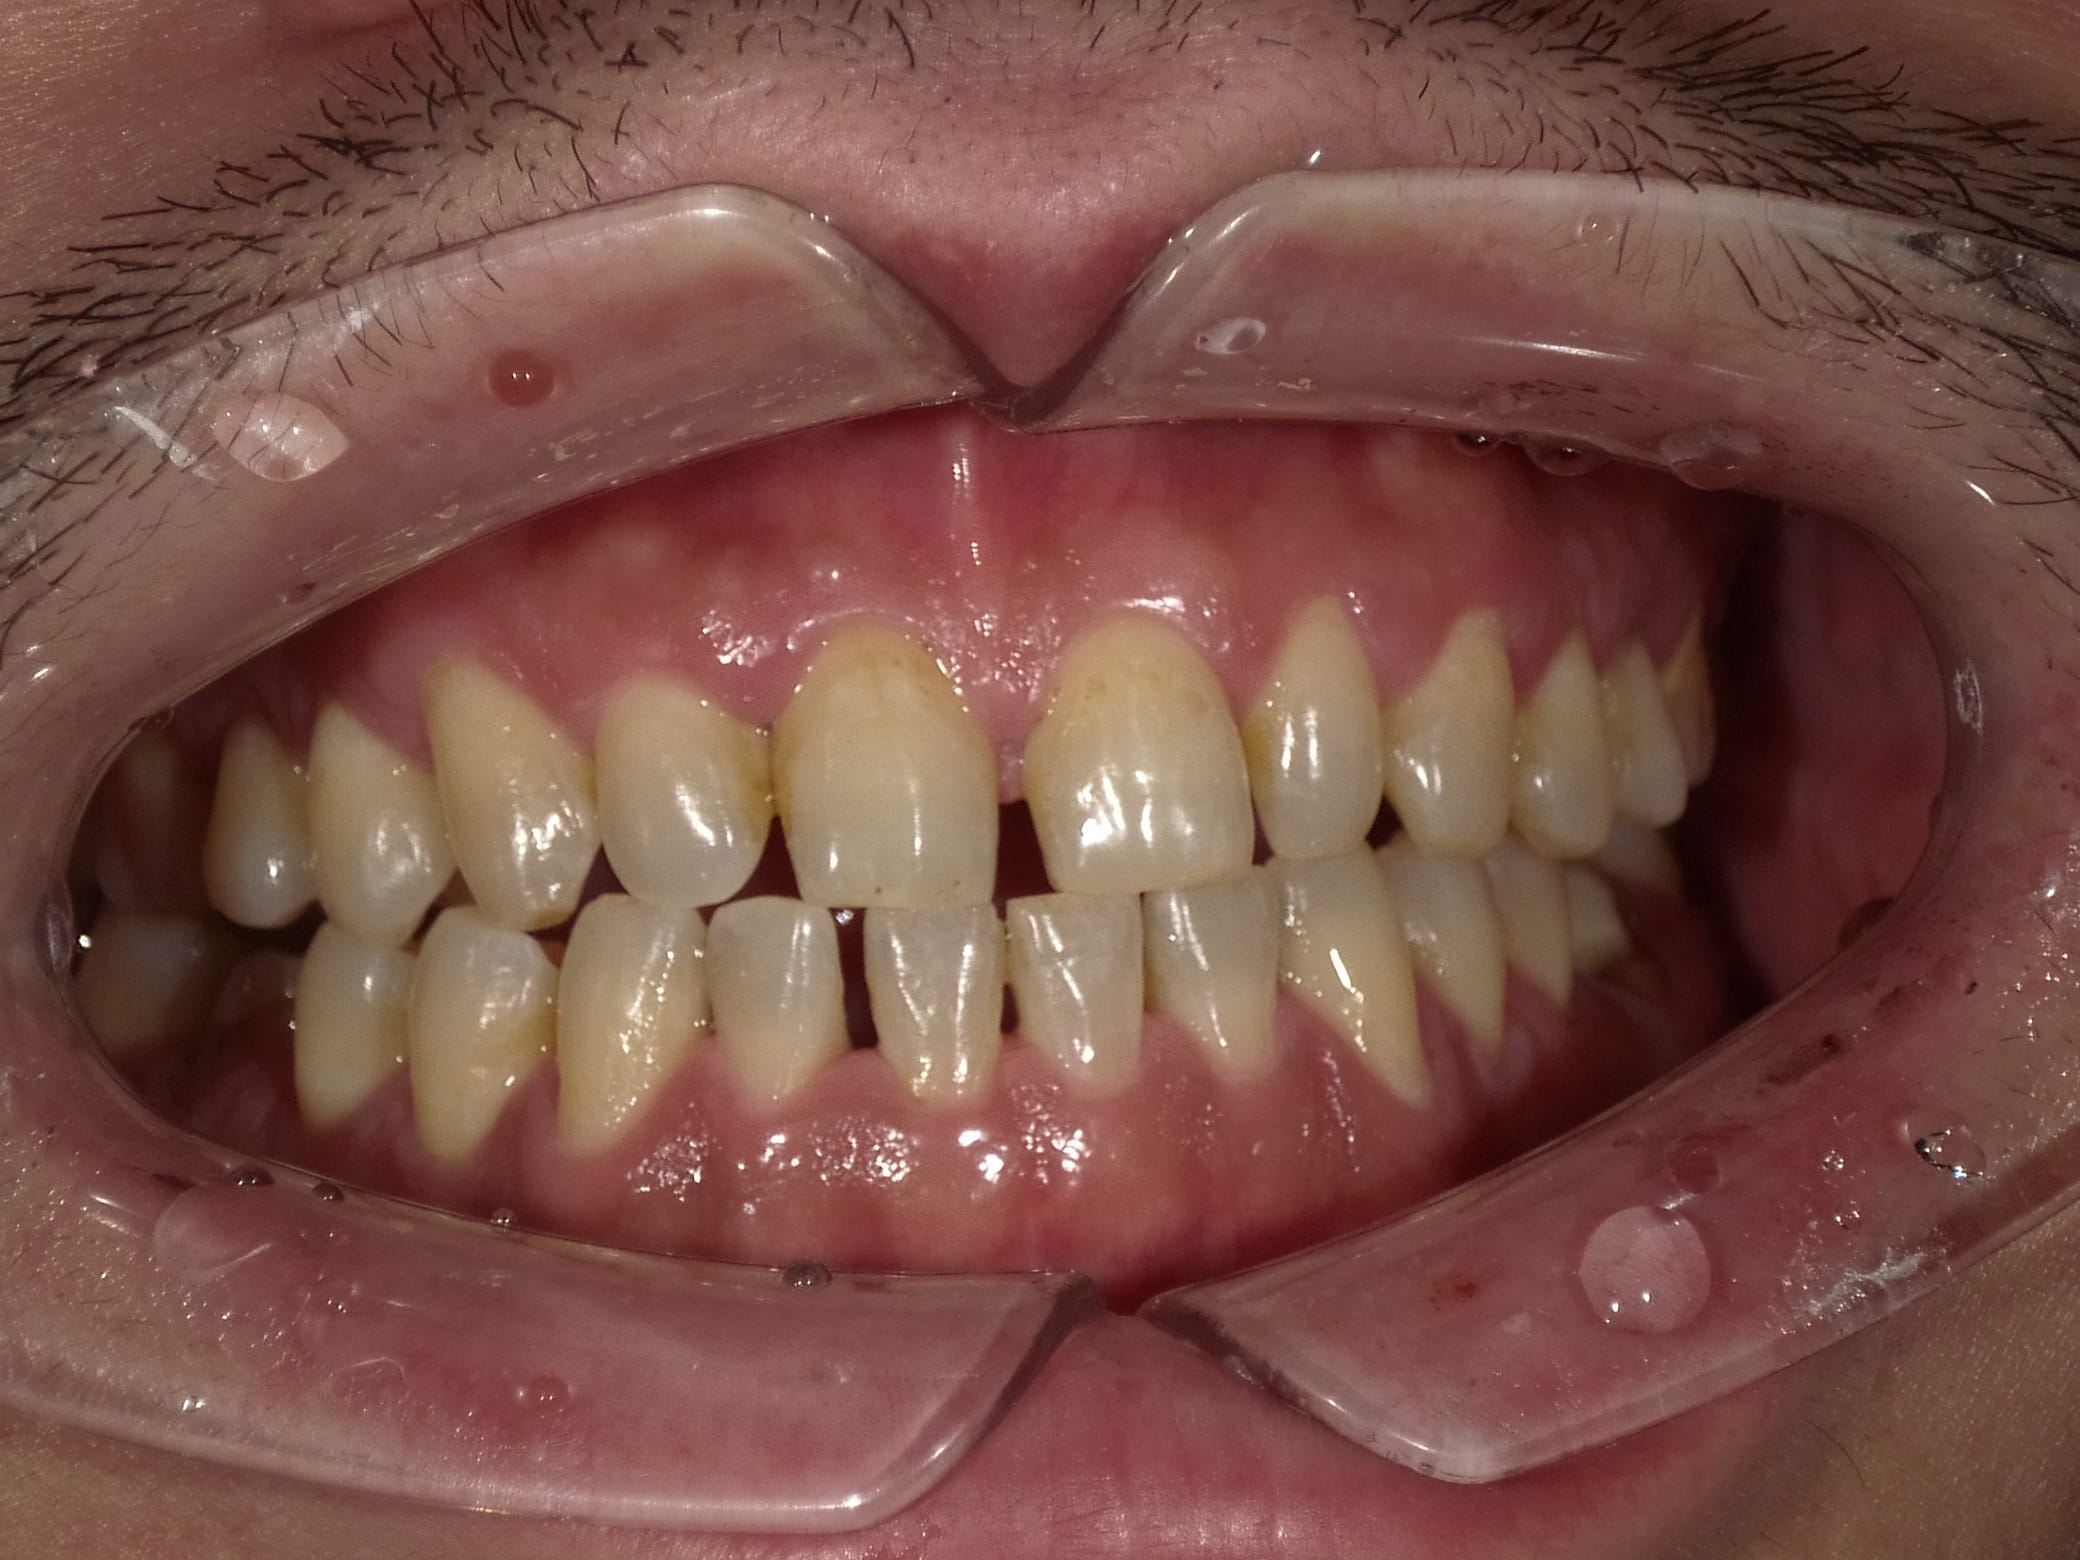

Case033

前歯が虫歯なのと、保険のプラスチックで大きく治療されていて色が悪いこと、歯並びが出っ歯気味であることを気にしてセラミックにしたいという主訴で来院された患者様です。

虫歯が大きかったところは神経治療をきちんと行い、

初診時を含めてトータル4回のご来院で完了です。

今回は前歯を下げる、歯列を整える、白すぎず自然に綺麗に見える色というご希望に沿って治療しました。

ご興味のある方はいつでもご相談ください。

担当 理事長 佐藤 悠野